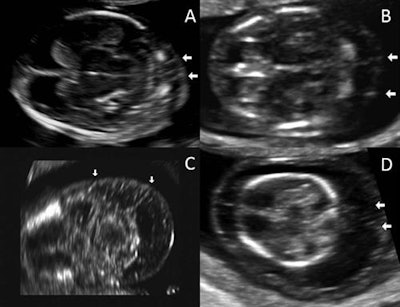

The researchers retrospectively reviewed the electronic medical records of 3,275 patients who had received first-trimester genetic screening and delivered babies at the Texas Children's Hospital Pavilion for Women between November 2011 and December 2014. They defined nuchal septations as the presence of fine linear echogenic images in the fetal nuchal translucency, which extended from the fetal skin to the tissues underneath. In addition, the presence of nuchal septations and increased nuchal translucency was considered to represent cystic hygroma.